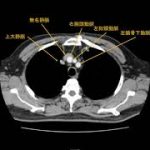

大血管(大動脈、大静脈、肺動脈、肺静脈)気管支、食道の位置関係を確認しましょう。 終了後は、受講登録のアンケートと小 ...